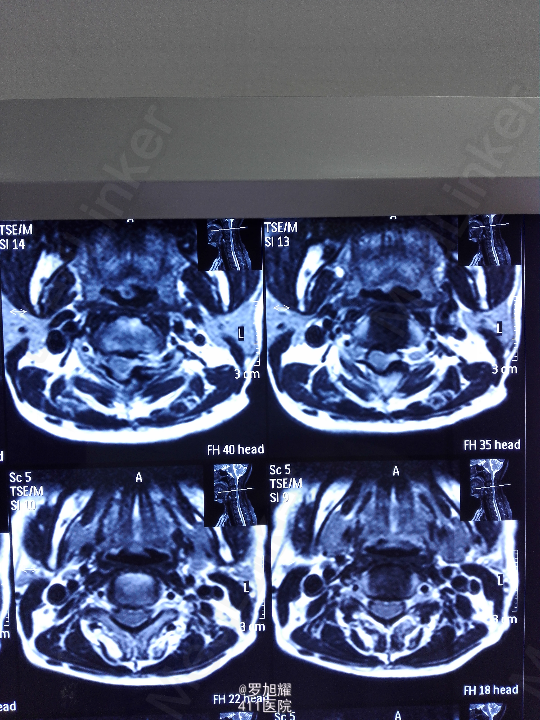

右侧躯体麻木1年,右上肢及下肢麻木2月余。 查体:颈椎活动受限,右上肢肘关节以远痛温觉减退,右侧胸4平面以下痛温觉及触觉减退,四肢肌力尚可,右侧霍夫曼征阳性,右侧上下肢所有腱反射亢进。 颈椎X线示:颈2椎板棘突缺如,颈3棘突肥大增高。 颈椎CT示:颈2椎板棘突缺如,颈3棘突肥大增高,颈2/3椎间盘突出,左侧颈2残留部分椎板进入椎管。枢椎齿突增生,寰枢关节退变。 颈椎MRI示:颈2/3椎间盘突出,左侧颈2椎板进入椎管,颈髓受压变性。

查体:颈椎活动受限,右上肢肘关节以远痛温觉减退,右侧胸4平面以下痛温觉及触觉减退,四肢肌力尚可,右侧霍夫曼征阳性,右侧上下肢所有腱反射亢进。 颈椎X线示:颈2椎板棘突缺如,颈3棘突肥大增高。 颈椎CT示:颈2椎板棘突缺如,颈3棘突肥大增高,颈2/3椎间盘突出,左侧颈2残留部分椎板进入椎管。枢椎齿突增生,寰枢关节退变。 颈椎MRI示:颈2/3椎间盘突出,左侧颈2椎板进入椎管,颈髓受压变性。